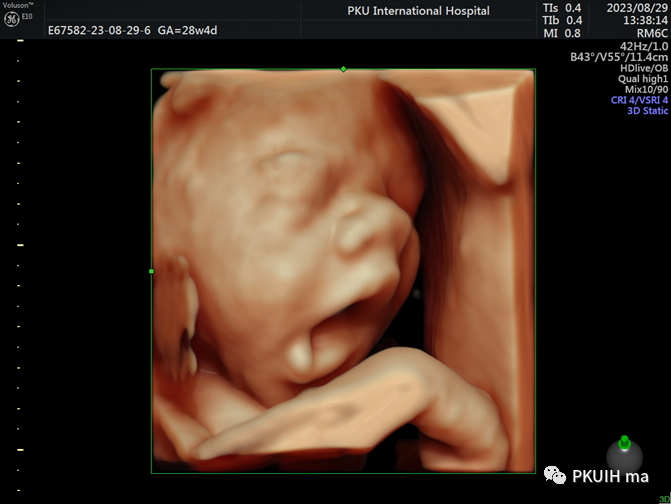

小宝宝在打哈欠